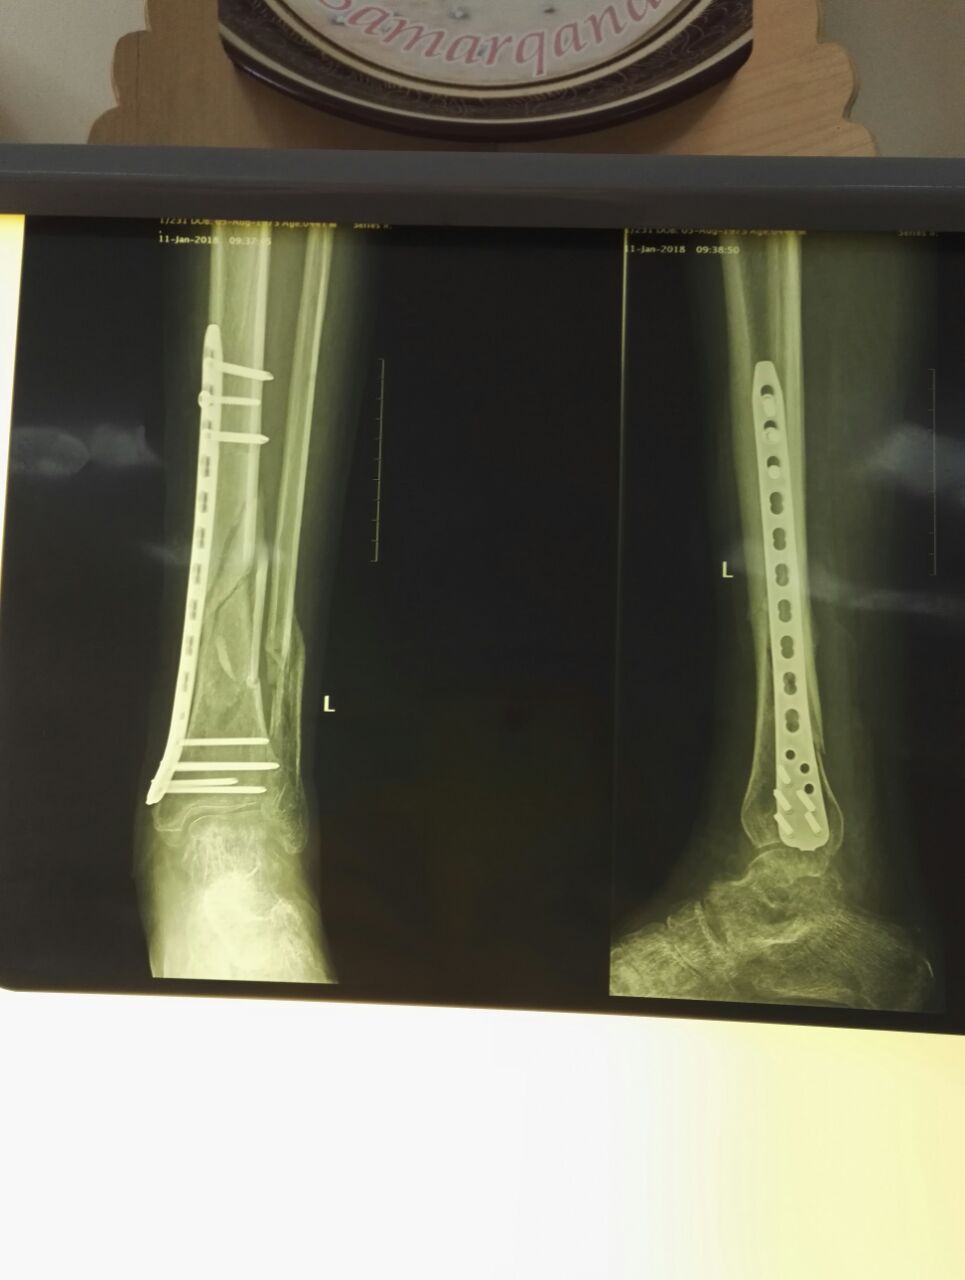

[Ortho] Гнойные осложнения после остеосинтеза

7 п╪п╣я│. п╫п╟п╥п╟п╢ - MIPO

п╖п╣я─п╣п╥ п╪п╣я│я▐я├ - п©п╬я┌п╣п╨п╩п╬. п▓я│п╨я─я▀п╡п╟п╩п╦, п©п╣я─п╣п╡я▐п╥я▀п╡п╟п╩п╦.

п╖п╣я─п╣п╥ п╫п╣я│п╨п╬п╩я▄п╨п╬ п╢п╫п╣п╧ п©п╩п╟п╫п╦я─я┐п╣п╪ п╬п©п╣я─п╟я├п╦я▌.